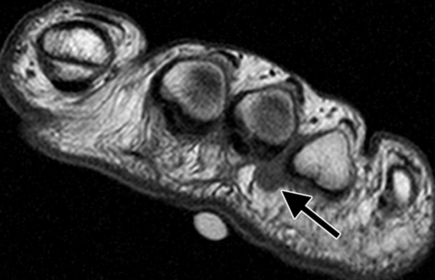

What does the arrow show? What could this be? | Teardrop-shaped hypointense lesion in third interspace. Could be morton's neuroma |